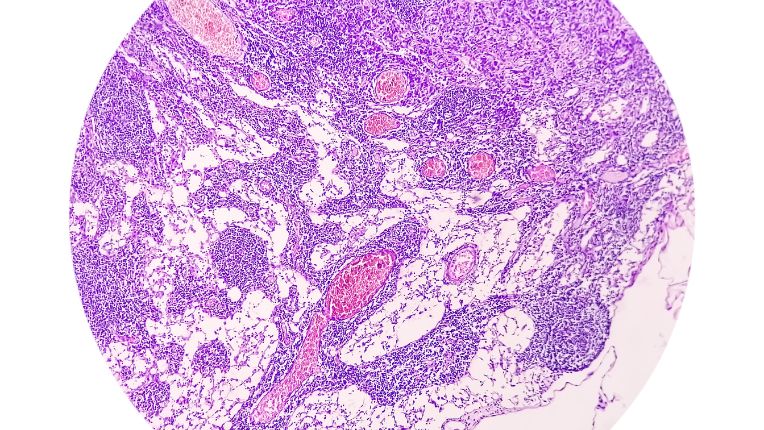

L'adénocarcinome est un type de cancer. Il s'agit d'une tumeur maligne qui se crée à partir d'un certain type de cellules, très répandues dans l'organisme : les cellules épithéliales glandulaires. L'épithélium est un tissu qui recouvre le corps et tapisse les organes dits creux : cela concerne, par exemple, l'appareil respiratoire, le système digestif, les organes reproducteurs et urinaires. Le cancer du sein, le cancer de l'estomac, le cancer de la prostate, le cancer du pancréas, le cancer colorectal sont souvent associés aux adénocarcinomes. L'adénocarcinome représente une forme spécifique de carcinome.